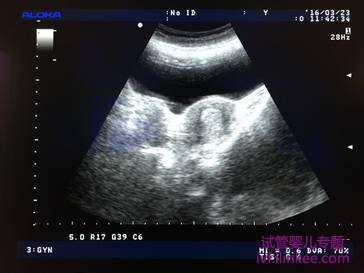

移植前为什么需要憋尿?如何正确憋尿?

膀胱内有适量尿液,腹部B超可以更容易看清子宫位置,请按照护士要求提前喝水,甜饮料憋尿最快。但必须注意,尿不是憋得越多越好,尤其后位子宫。膀胱内尿液太多,不但影响B超下子宫的观察,可能改变子宫的生理解剖位置,而且尿憋的太急会高度紧张,加上腹部探头按压,容易不由自主用力,这些都会人为增加胚胎移植的难度,降低成功率。所以憋尿以不感觉尿急憋不住为适宜,如等待手术时已感憋不住,请及时排出部分尿液,可在排尿时心里数数10下后结束。